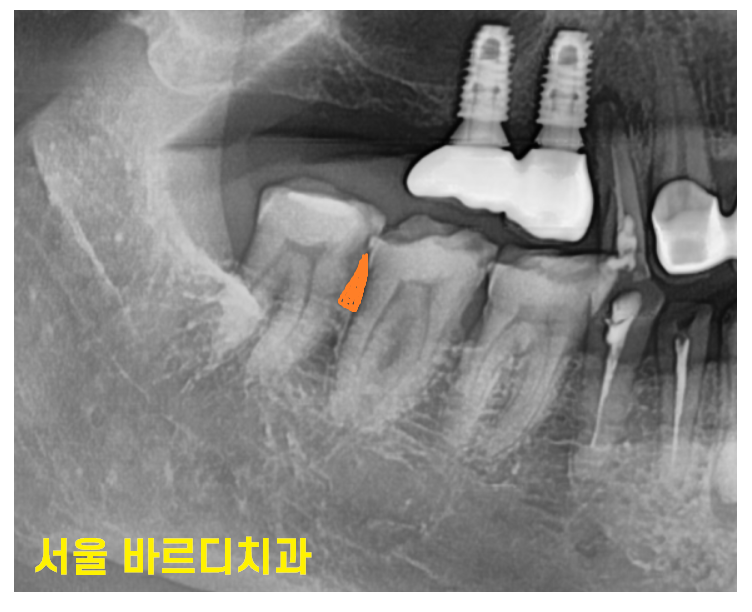

이번에는 위 아래로 변화 케이스입니다.

오늘 환자분처럼 위에 치아가 없는 경우 치아 올라옴

아래 치아가 없는 경우 위에 치아 내려감 현상이 생겨요.

두번째 문제점은 나중에 임플란트를 하게 되었을 때

높이가 나오지 않게 될 수 있습니다.

231019

반대편 치아 올라옴으로 앙 물었을 때

높이가 안나오는거죠~

이렇게 되면 임플란트를 해도

보철 머리 길이가 짧아지거나

반대편 치아를 신경치료 후

보철을 할 때 치아를 깎아 높이를 맞춰주거나...

해야합니다.